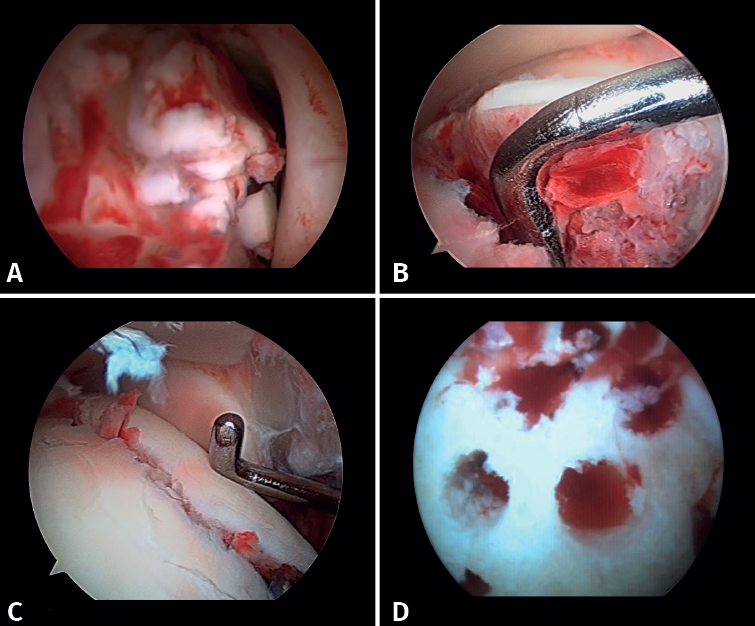

Lee has described a novel technique using a drill guide with ankle arthroscopy for the reduction of joint fragments in posterior malleolus fractures. In particular, this technique is beneficial for patients with trimalleolar fractures who have a depressed joint fragment, as it allows anatomical reduction and minimizes the need for extensive incisions(11). - Extraction of loose bodies. The presence of loose bodies within the joint is a common finding in ankle fractures. One-third of all arthroscopy patients had intra-articular loose bodies removed during surgery (24 out of 71cases)(12). Arthroscopy allows the precise removal of intra-articular loose bodies, which can cause pain, blockage or limitation of mobility, and damage to the joint cartilage(13).

- Management of chondral injuries. The literature reports the presence of chondral injuries in 34-91% of all ankle fractures. These lesions are frequently located in the talus and are most common in severe fractures, such as Weber C and PER fractures. Patients with cartilage lesions were 3.5 times more likely to develop radiographic osteoarthritis (Kannus arthritis score < 90) and 5 times more likely to have an unfavorable long-term clinical prognosis (American Orthopedic Foot and Ankle Society [AOFAS] score < 90)(14).

If possible, we reinsert unstable osteochondral fragments (Figure 3). In chondral lesions where it is not possible to reinsert the fragment, cartilage repair stimulation techniques can be used(5,13).